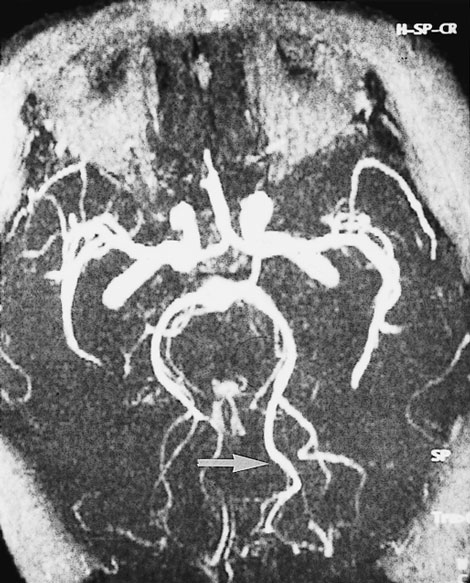

Computed tomography (CT) brain scan was performed three hours after the completion of coronary angiography. No additional contrast was used. The CT brain scan (Box 1) showed marked bilateral contrast enhancement of the occipital lobes and no evidence of a cerebral haemorrhage. Intravenous heparin treatment was commenced. By the following day, she was able to see shapes and shadows but had persistent headache and nausea. A repeat CT brain scan did not show any residual abnormality. During the next 48 hours, her vision progressively returned. She described flashing lights in her right eye and had evidence of right homonymous hemianopia. Magnetic resonance imaging (MRI) showed increased signals in the grey matter of the medial aspect of the left occipital lobe, on a background of longstanding mild ischaemic changes consistent with her age and cardiac risk factors (Box 2A). Magnetic resonance angiography (MRA) showed patency of both posterior cerebral arteries, with dilatation of branches supplying the left occipital lobe (Box 2B). Heparin therapy was ceased, as there was no evidence of acute thromboembolism or acute infarction. She fully regained her vision five days after coronary angiography.

These mechanisms seem possible in our patient, and they were supported by the results of imaging studies. There were bilateral occipital lobe changes when she had clinical cortical blindness (Box 1), representing oedema and passage of contrast across the blood–brain barrier. Cortical blindness is synonymous with bilateral homonymous hemianopia from involvement of the occipital cortex.1 When our patient was recovering and exhibiting right homonymous hemianopia, there were MRI changes in the left occipital gyrus, and differences in the calibre of the vessels on the two sides (Box 2).

B: A magnetic resonance angiogram (MRA) at the same time shows that both posterior cerebral arteries are patent. The peripheral branches on the left side are larger (arrow).

B: A magnetic resonance angiogram (MRA) at the same time shows that both posterior cerebral arteries are patent. The peripheral branches on the left side are larger (arrow).